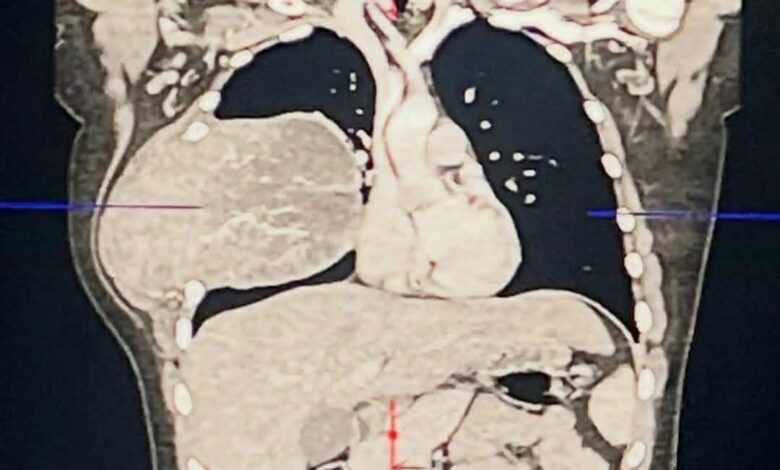

الفحص السريري يكشف الحقيقة الصادمة

مع الإصرار، تم إجراء فحص دقيق للصدر ومنطقة الإبط، لتظهر المفاجأة: الحالة كانت أكبر بكثير مما تم تشخيصه سابقًا.

أوضح أوضح وجود مشكلة حقيقية تستدعي الانتباه والمتابعة، وهو ما يؤكد أن تجاهل الألم المزمن قد يؤدي إلى تأخير تشخيص حالات خطيرة.